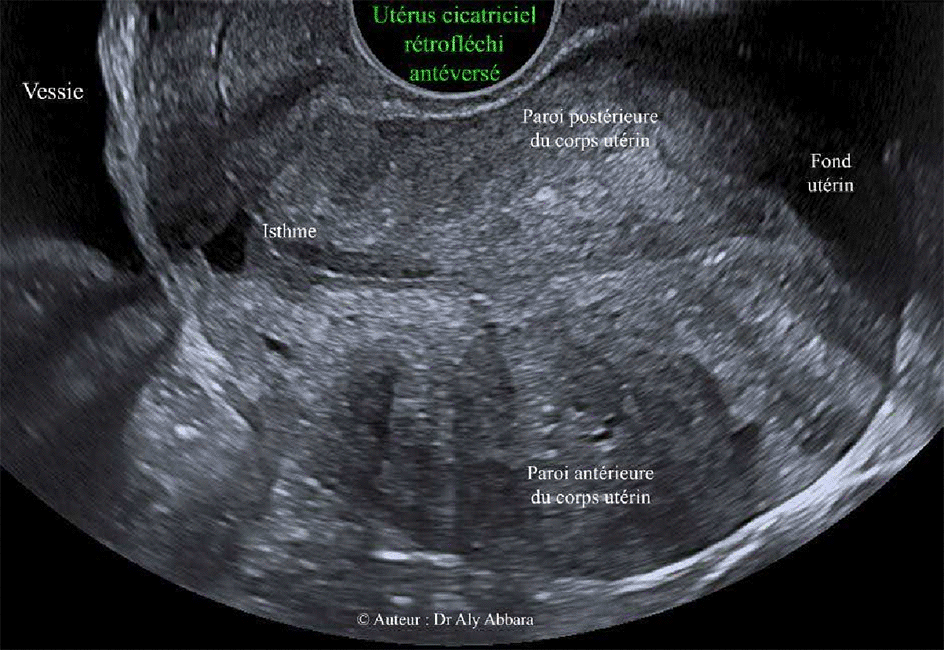

Utérus cicatriciel rétrofléchi antéversé

Images échographiques animées montrant un utérus cicatriciel rétroversé antéfléchi

Antécédent : césarienne segmentaire transversale